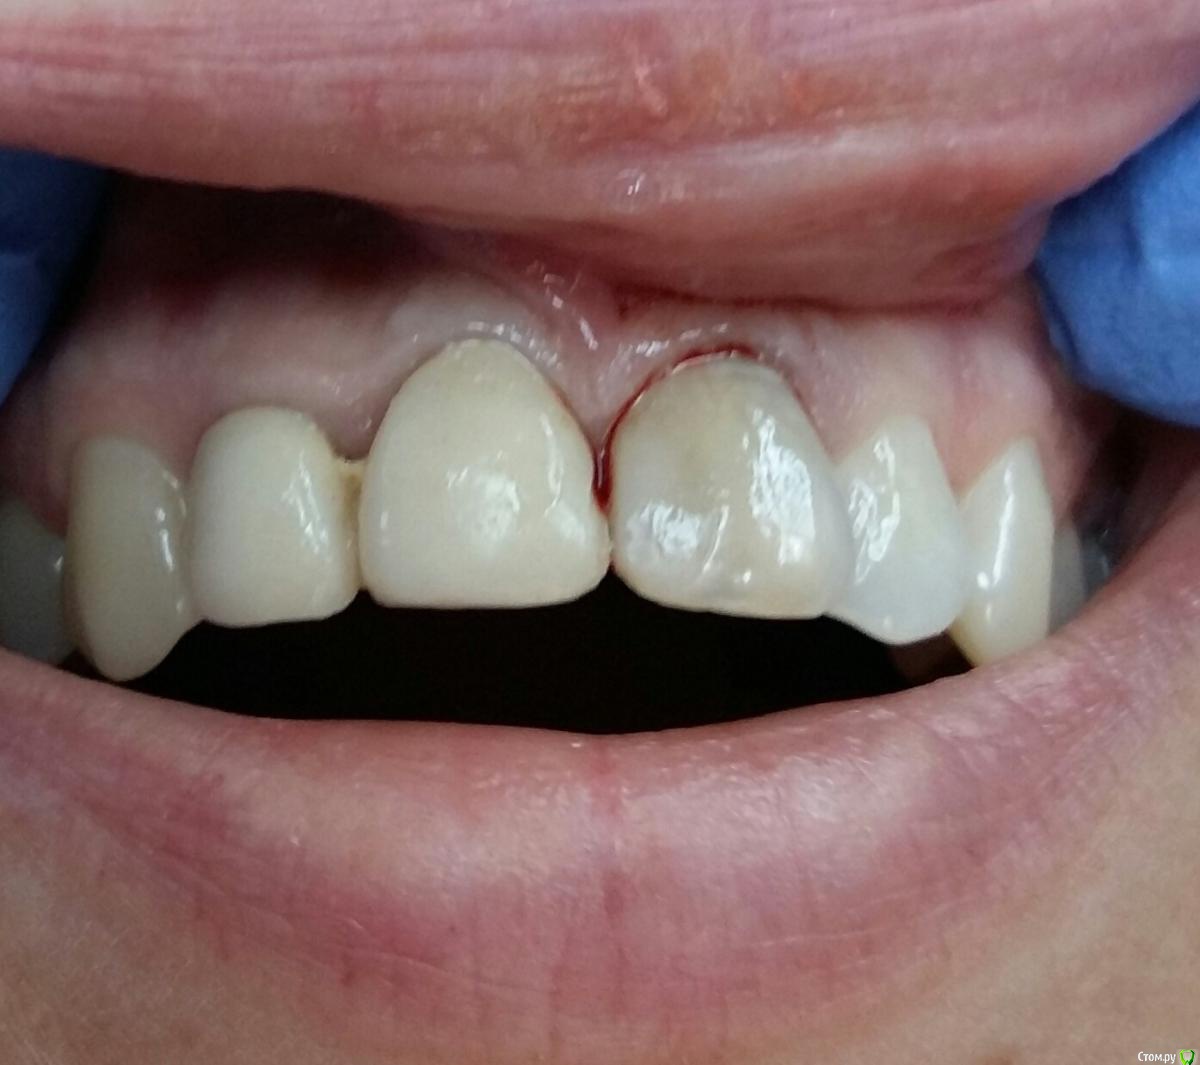

StomV Опубликовано 9 ноября, 2017 Поделиться Опубликовано 9 ноября, 2017 Итоговый результат нравится,хорошо получилось. Ссылка на комментарий